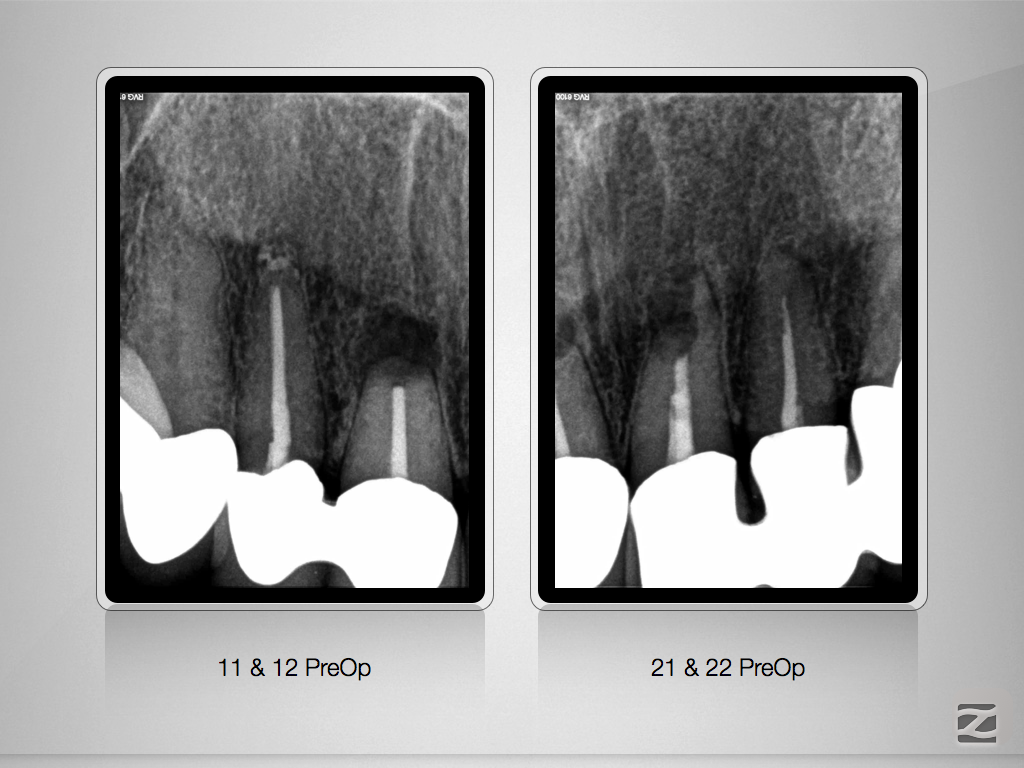

Saving Hopeless Teeth – Zustand nach WSR